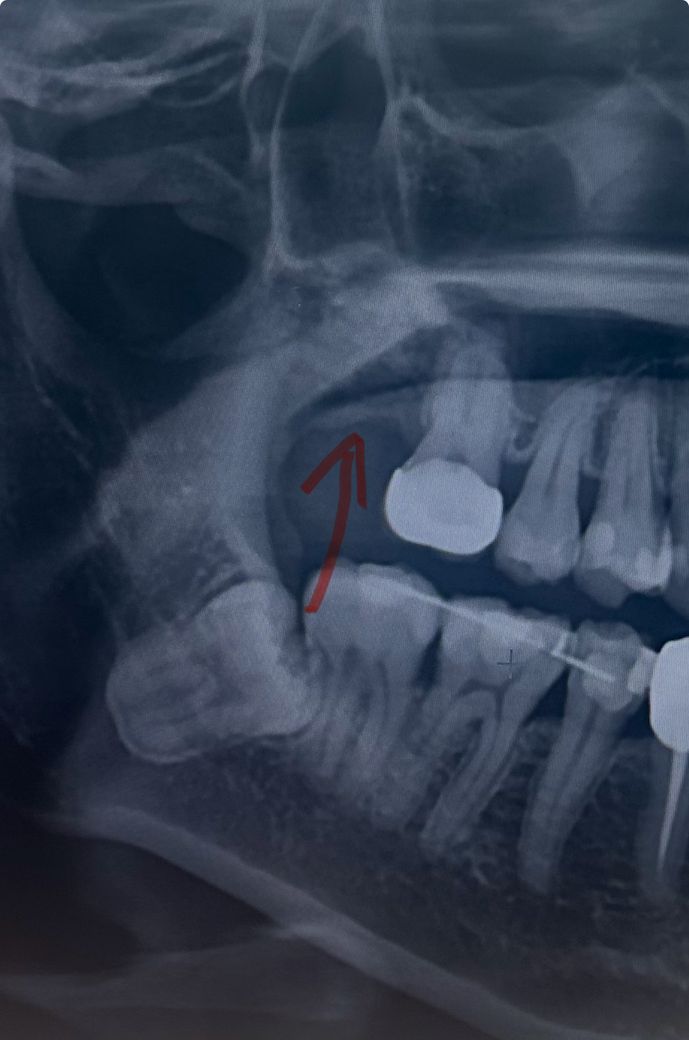

발치 즉시 뼈이식한지 한달반 지났습니다. 뼈가 생기고 있나요?

위턱 맨안쪽 어금니 발치와 동시에 뼈이식 했습니다.

다른 진료를 받으려고 타병원에서 찍은 엑스레이 사진을 보니, 뼈가 자라고 있는건지 모르겠습니다.

[뼈이식 후 한달 반 사진]

사진 상으로는 뼈가 잘 형성되고 있는 것으로 보입니다. 조금 더 기다리면서 지켜봐야 할 듯 합니다.

사진상으로 보면 뼈가 조금씩 차고 잇는것처럼 보입니다. 한달정도면 조금더 기다리셔야될것같습니다.

뼈이식을 해도 뼈가 더 자라지는 않으면 빈공강을 메꾸게 됩니다. 사진상에서 빈공간은 없어진 것으로 보이며, 뼈가 단단하게 굳었는지는 x-ray에서는 확인 안됩니다.